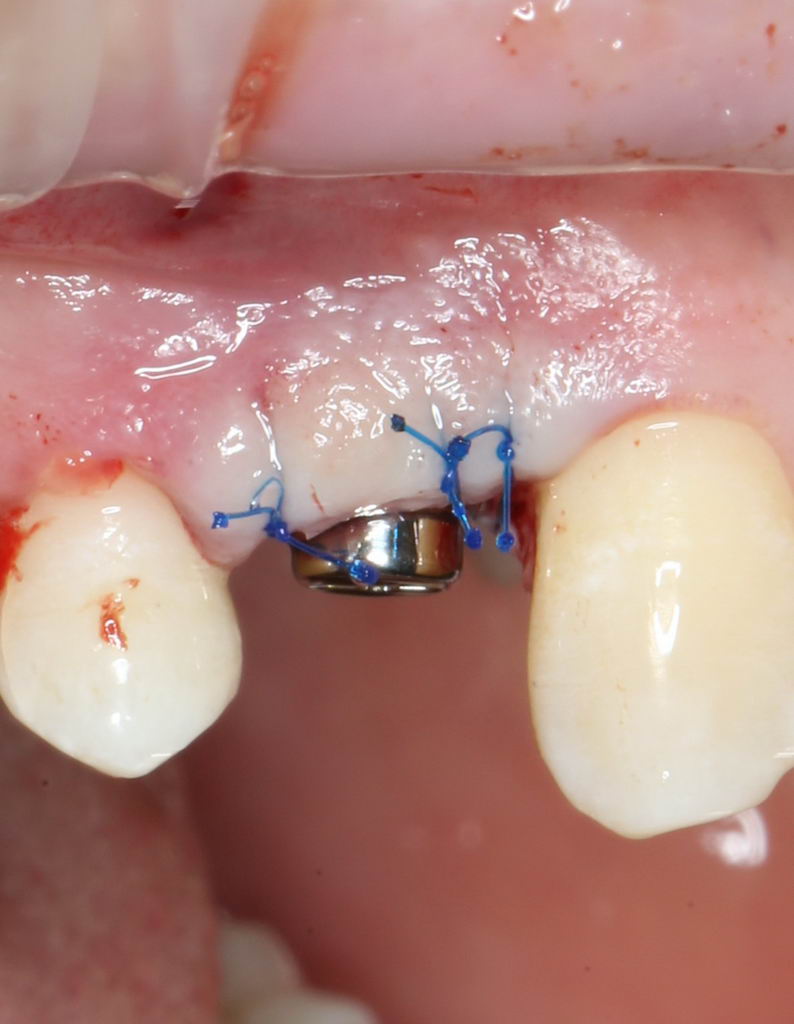

Для окончательного формирования десневого контура, осталось только наложить швы.

Наложение швов.

Помните, в самом начале операции мы планировали наложение швов с учётом будущего вестибулярного смещения лоскута? Так вот, теперь у нас есть возможность не просто сместить, но и зафиксировать вестибулярный лоскут. Делается это, так сказать, с подворотом края снаружи:

Обратите снимание, что альвеолярный отросток в этой области стал более объемным. Этого удалось добиться без всяких остеопластических операций или гингивопластики, путём простого перемещения тканей.

Всё. Операция закончена: